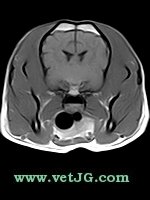

RESONANCIA MAGNÉTICA

AXIAL